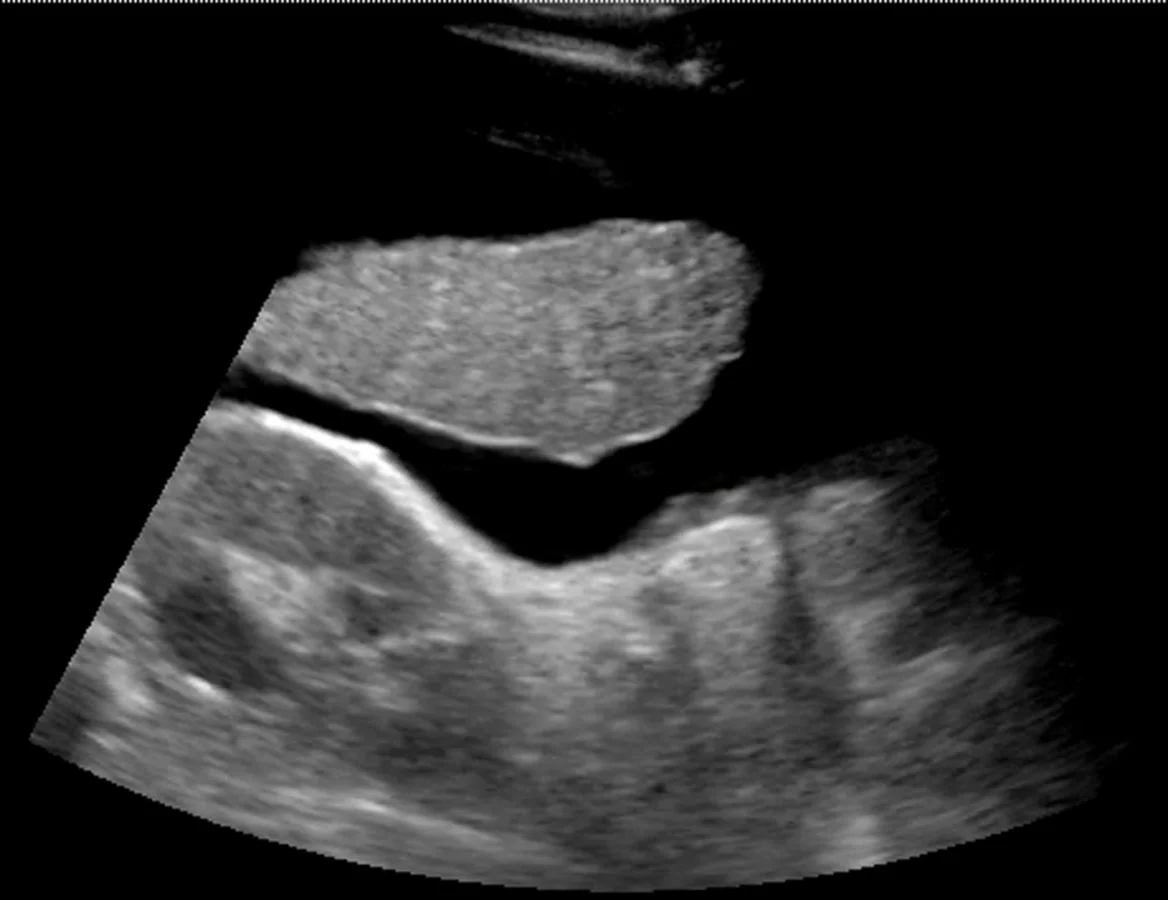

The RUQ is the most sensitive region for free fluid in comparison to the other eFAST views.

The RUQ should be divided into 3 zones.

1. Above/Below the diaphragm,

2. Morrison’s pouch (hepato-renal recess)

3. Para-colic gutter: Around the inferior hepatic edge/inferior pole of kidney

The key is to know your landmarks, and STOP, STAY and widely FAN through each zone well, adjusting your depth as necessary to keep the area of interest centered on your screen.

Start high to stay and fan (anterior to posterior) around the diaphragm. Then, SLIDE down into another rib space, stop, stay and fan around the entire kidney. An additional rib space may be necessary to evaluate the para-colic gutter.

Tips for RUQ Diaphragm View :

The liver may be easily seen, but the diaphragm can be more difficult, especially if it’s behind a rib shadow, inspiration views can help. This lowers the diaphragm into your view and allows visualization of the thoracic cavity for haemothorax/pleural fluid as well as sub-diaphragmatic peritoneal fluid.

Visualization of the spine shadow traveling in the lower part of the screen will normally stop at the diaphragm with a mirror image artifact illustrated in the thoracic cavity. However if the spine is able to be seen above the diaphragm...this is suggestive of pleural fluid